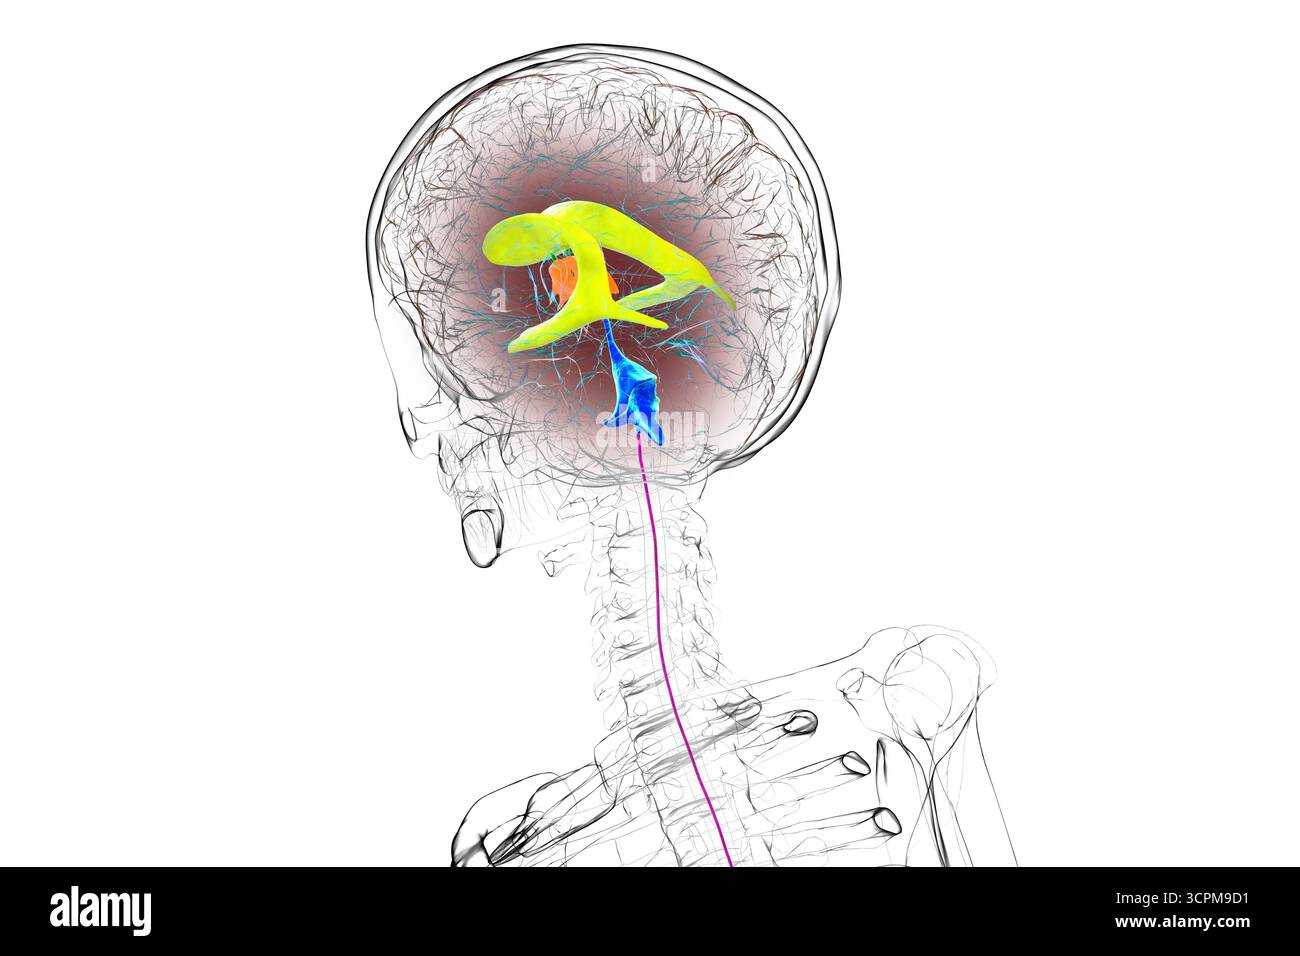

RF3CPM9D1–Abbildung des menschlichen Gehirns mit farbigen Ventrikeln: Lateral (gelb), dritter (orange), vierter (blau), interventrikuläres Foramen (grün), cerebral

RF3CPM9CD–Abbildung des menschlichen Gehirns mit farbigen Ventrikeln: Lateral (gelb), dritter (orange), vierter (blau), interventrikuläres Foramen (grün), cerebral